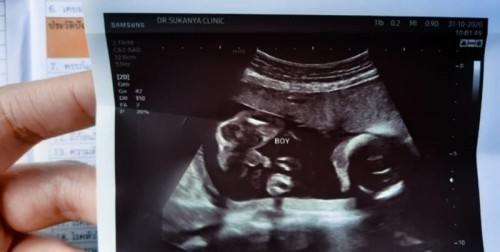

อยากได้ลูกสาว แต่ได้จู๋มาเลยจ้า ตอนแม่ๆซาวด์ช่วง20weekน้องน้ำหนักกี่กรัมกันบ้างคะ 😊😊 ของแม่บ้านนี้ 411g.จ้า หมอบอกแอบจ้ำม่ำ😅

ซาว 21w 403 กรัมคะ